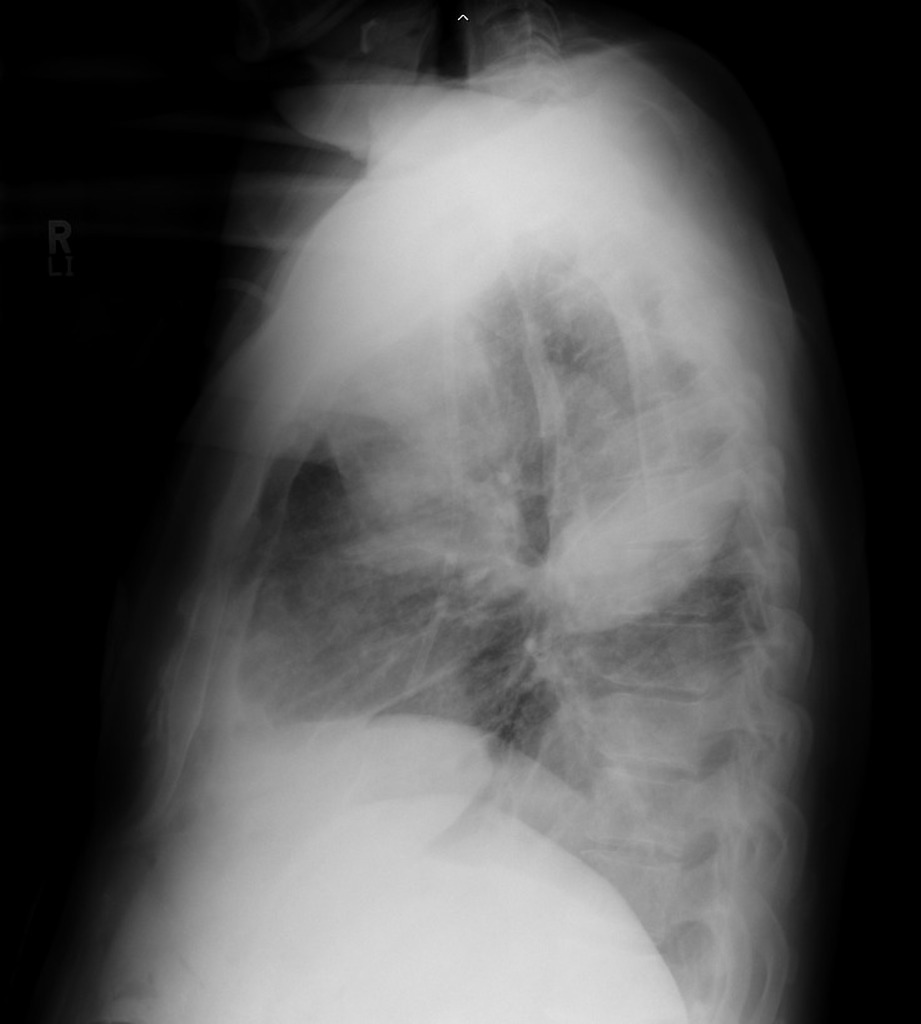

HOMEM, 50 ANOS, INTERNADO POR DISPNEIA + HEMOPTISE DE INÍCIO SÚBITO

áreas de opacidade em vidro fosco associadas a espessamento de septos interlobulares e intralobulares

HEMORRAGIA PULMONAR